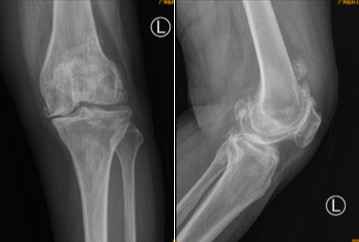

术前X光检查显示何阿姨左膝关节软骨完全磨损,髌上囊及股骨后髁大量骨赘增生,何阿姨尽管行动不便、疼痛难忍,却对手术顾虑较大。“如果不进行手术根治,日后不但难以行走,更会因为长期不运动,使得心肺功能下降,原有的高血压、糖尿病等基础疾病也难以控制。”张弛分析了手术的必要性和有效性,最终患者和家属一致决定进行手术,但手术的难题却也如同“拦路虎”一样出现。

术前X光片提示患者左膝关节软骨完全磨损,髌上囊及股骨后髁大量骨赘增生。

“经过完整的检查发现,患者不仅是关节的磨损和变形,大量骨刺堆积在股骨后髁造成她的关节屈伸受限,更为棘手的是,患者还合并痛风和糖尿病,还要同时在手术中清除关节内的痛风石,而糖尿病的患者一定要控制手术时间,防止感染几率升高。”张弛副主任医师解释说,“如何做到微创、快速、精准的完成手术成为最大的难题。”